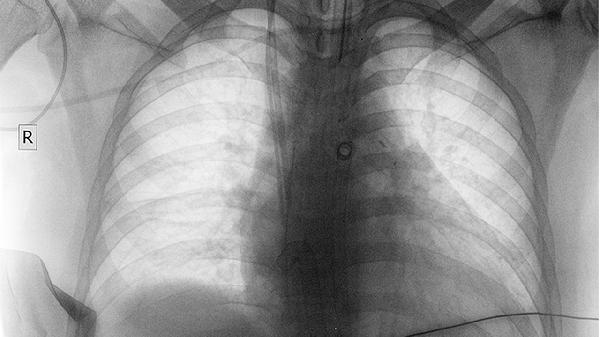

磨玻璃结节在CT影像上表现为类似磨砂玻璃的模糊阴影,密度低于实性结节但高于正常肺组织。左肺上叶尖后段属于肺叶的特定解剖位置,该区域结节需结合形态、大小及生长速度综合评估。多数情况下,直径小于8毫米且边缘光滑的结节可能与既往肺部感染、结核愈合后纤维化或少量肺泡出血有关,这类结节通常建议6-12个月随访复查。